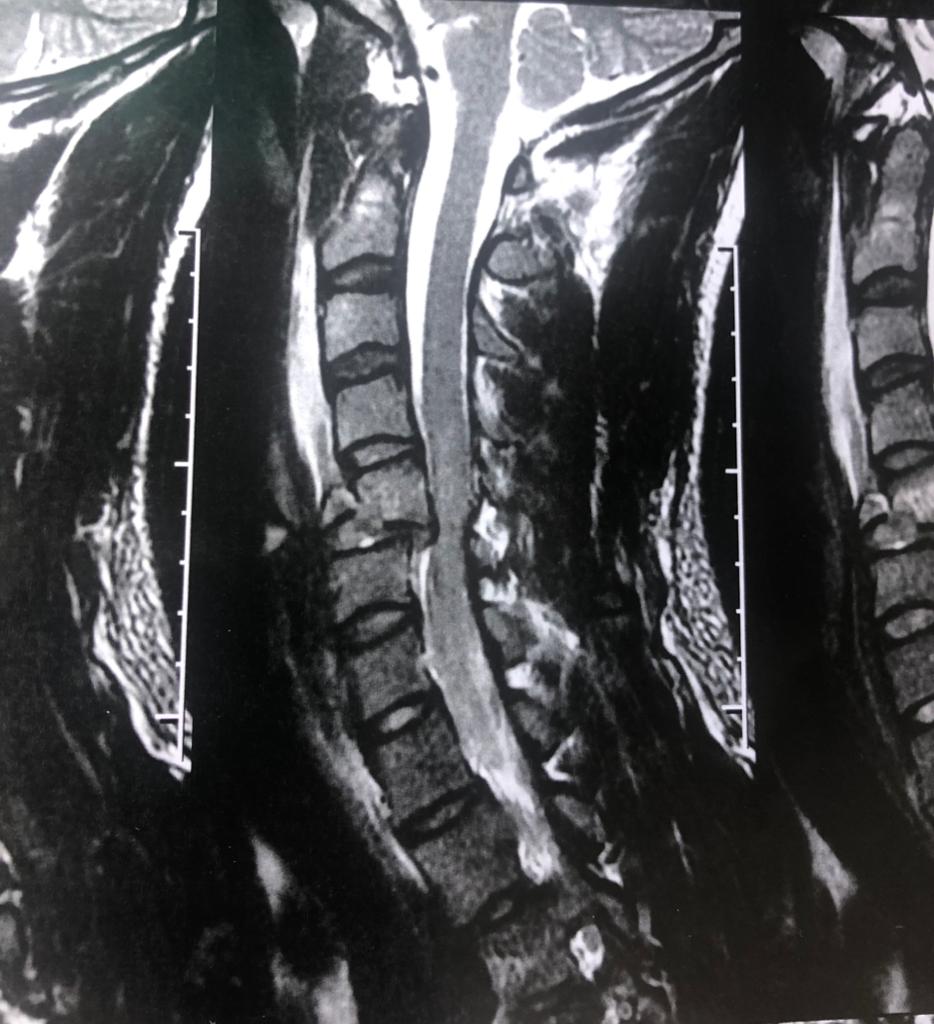

No dia 25 de setembro de 2019, o 9º Grupamento de Bombeiros atendeu uma vítima de queda durante a prática de exercícios físicos em uma academia. João Vitor, de 20 anos, apresentava além de contusões, dormência e imobilidade em todo o corpo abaixo do pescoço. Deslocaram até o local, a ambulância, a viatura do médico de área e do oficial de área.

Impactos de uma queda, assim como outros acidentes, podem causar lesões na coluna, podendo provocar paraplegia ou tetraplegia, além de outras complicações. O atendimento a uma vítima com sinal de dormência no corpo requer uma atenção especial, evitando qualquer tipo de movimentação que possa causar uma dessas consequências.